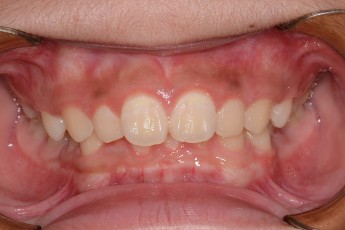

BEFORE & AFTER